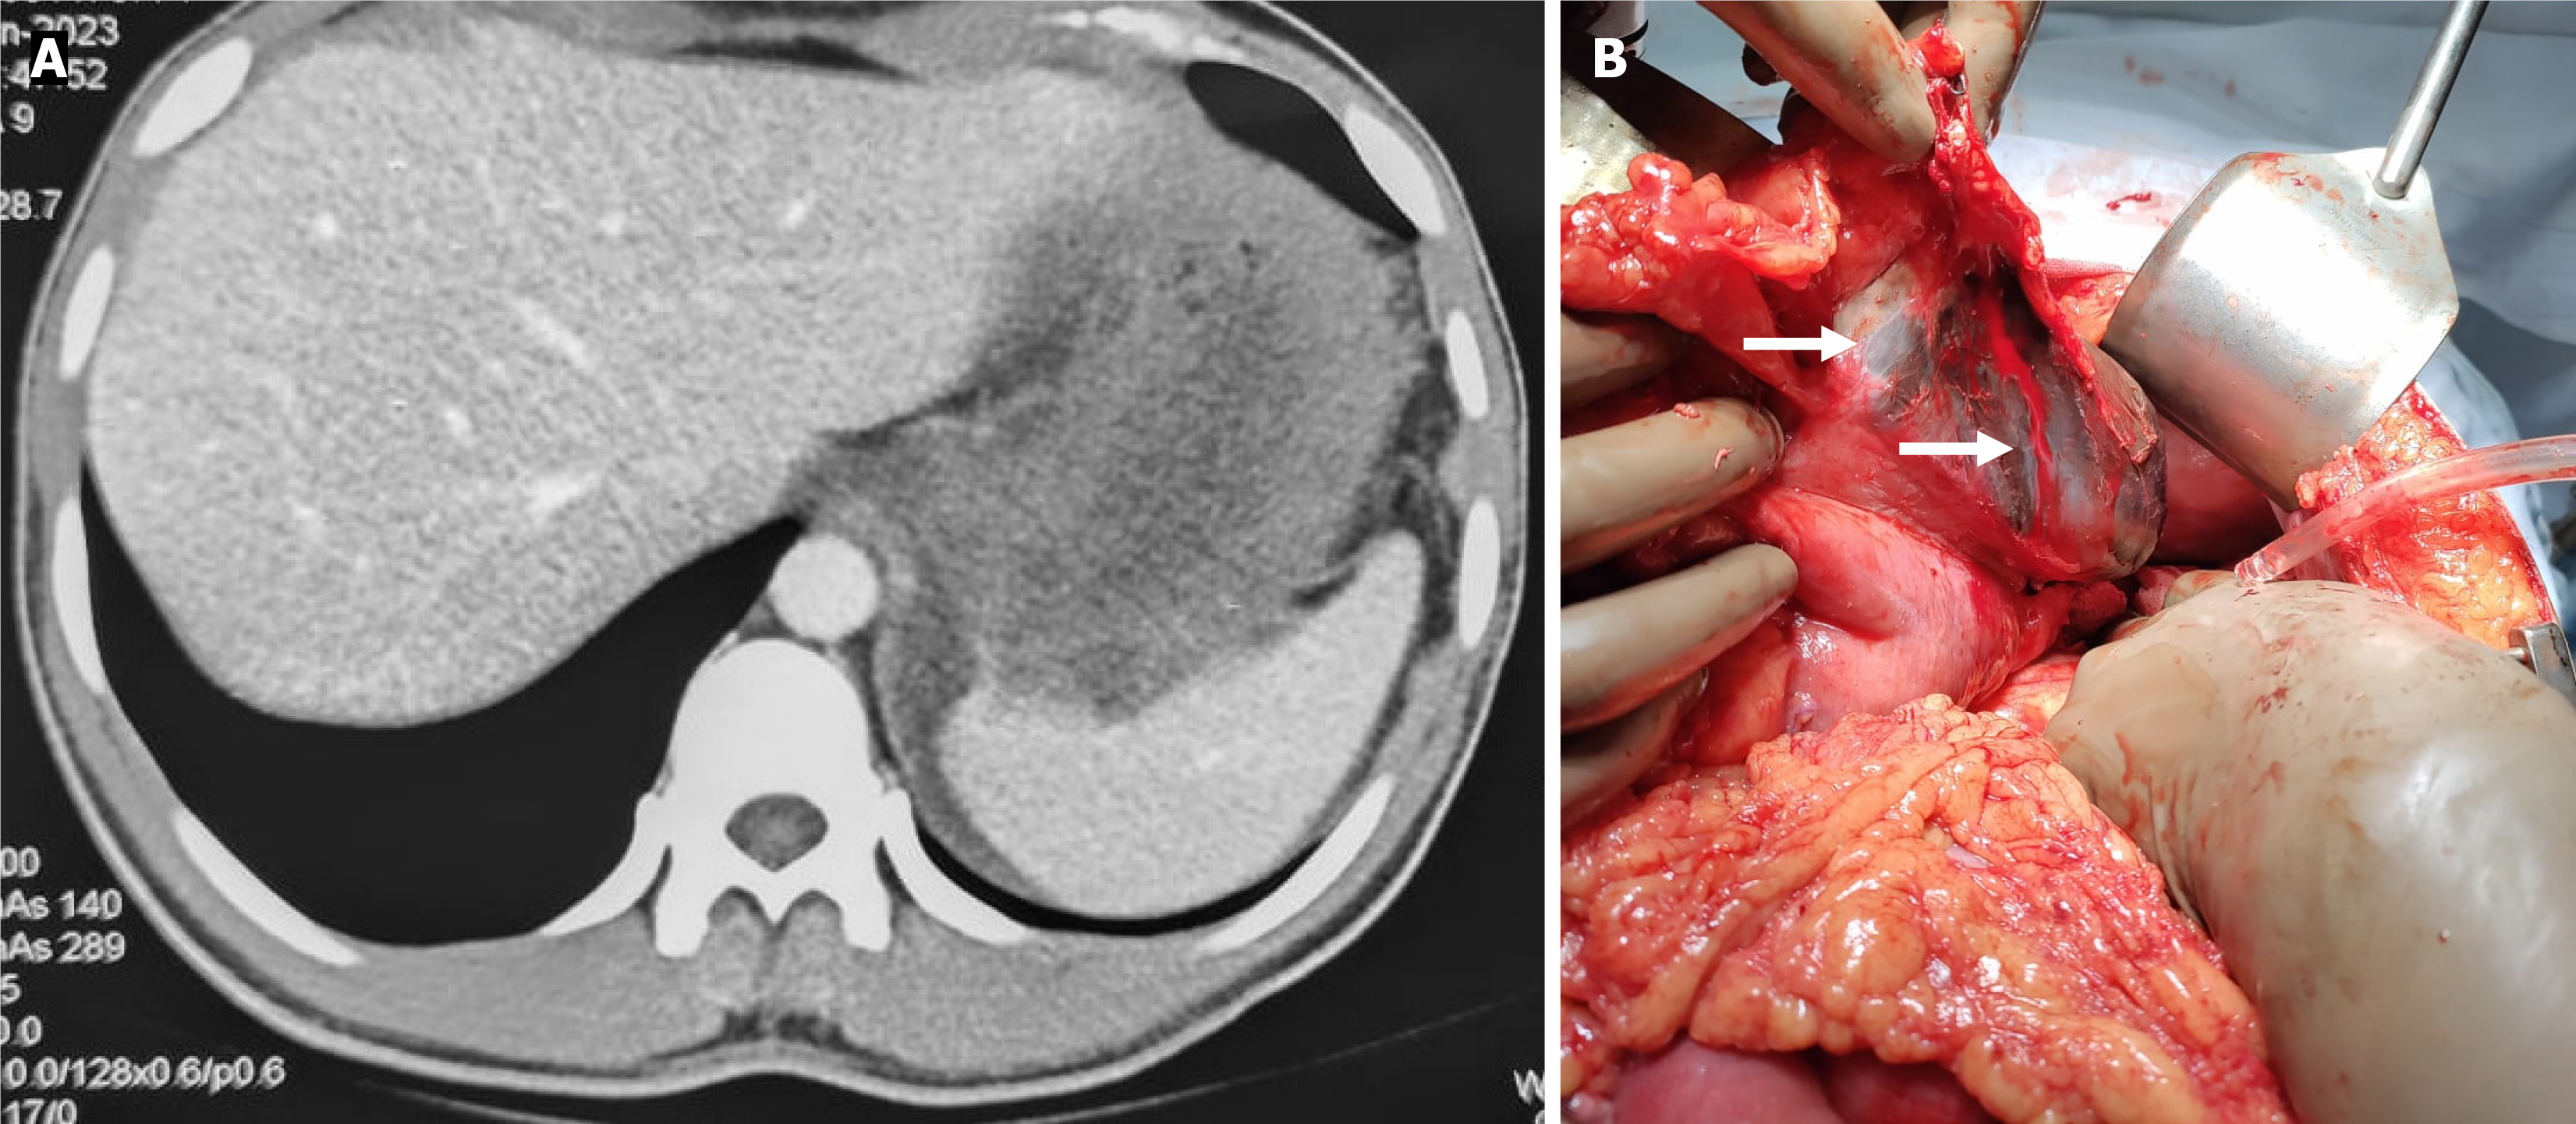

CT grading systems in caustic injury: Several CT-based grading systems have been proposed to standardize the radiological assessment of caustic injuries, the most commonly cited being those by Ryu et al[5] and Chirica et al[7] The Ryu system is a 4-point classification based on esophageal wall thickening and peri-organ collections, with additional assessment of surrounding tissue infiltration and inflammation (Table 2). In contrast, the Chirica system is a simplified 3-point classification that evaluates wall thickening and enhancement, while also incorporating peri-visceral inflammatory changes (Table 2 and Figure 3). The Chirica grading is versatile, as it can be applied to the esophagus, stomach, or other hollow organ, whereas the Ryu grading is specific to esophageal injury. Both systems are useful in predicting stricture development of the esophagus, but Chirica grading also provides valuable short-term prognostic information, including the likelihood of intensive care unit admission and surgical exploration in cases of impending perforation[7].

| Grade 3 | Transmural necrosis, as shown by the absence of postcontrast wall enhancement with surrounding soft tissue inflammation | Moderate injury; risk of stricture formation; close monitoring required |

In contrast, studies applying the Chirica grading system have shown improved predictive performance of CT, particularly for identifying necrosis and stricture formation. In a cohort of 120 patients, Chirica et al[7] reported that 19 (15.8%) had injuries overestimated as necrosis on endoscopy, whereas CT correctly excluded necrosis and avoided unnecessary surgical exploration. The same group also demonstrated superior performance of CT compared to endoscopy in pre

Overall, the available evidence suggests that while endoscopy remains more sensitive for detecting mucosal injury and predicting early mortality, CT offers greater specificity for identifying transmural necrosis, stricture risk, and extra-luminal complications such as perforation, mediastinitis, and peritonitis. Importantly, CT may underestimate subtle mucosal changes that are better visualized endoscopically. Thus, the two modalities are best viewed as complementary: Endoscopy remains the gold standard for mucosal grading, whereas CT provides crucial information on depth of injury and extra-luminal pathology, enhancing prognostic accuracy and guiding surgical decision-making.